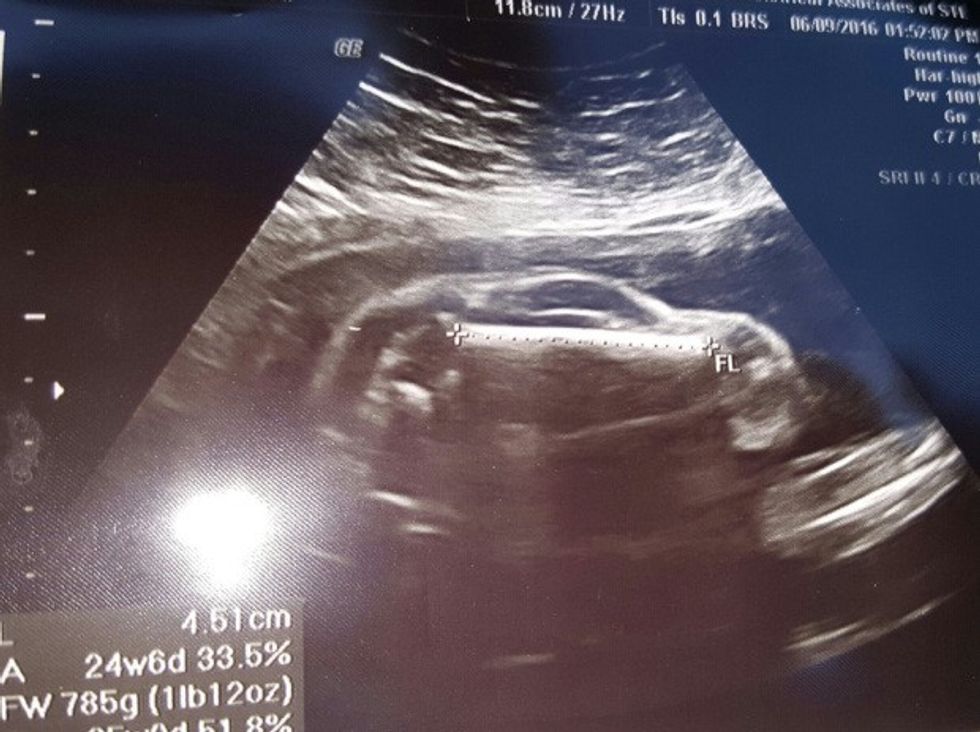

Por kur, Redditor Breëhaus dhe bashkëshortja e tij vizituan mjekun dhe bën një ultrazë pas javës së 24-të të shtatzënisë, ata menjëherë arritën të identifikojnë formën që u shfaq në ekranin e ultrazërit, transmeton Telegrafi.

Por problemi qëndronte tek pamja, që dukej se po presin një veturë të vogël në vend të një foshnje.

Dhe natyrisht, se babai që ndihej krenar e kishte shpërndarë këtë imazh në internet, nën të cilin kishte shkruar se bashkëshortja tij është shtatzënë me një veturë sportive.

Natyrisht se bëhej fjalë për një gabim teknik, pasi mjeku më vonë ua kishte treguar fotografinë e vërtetë të ultrazërit /Telegrafi/